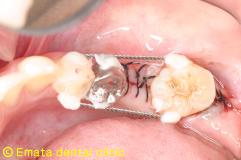

親知らずを移植歯に使用しました。大きさ、根の形態、歯根膜の状態、すべてに適応症の歯です。 |

| 歯牙移植手術 | |